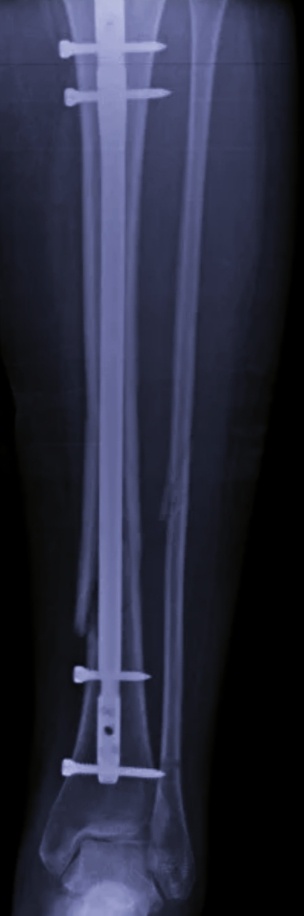

–Голень,-подсказала мне операционная медсестра.

-Гвоздь?

-Ага.

– Поняла.

Это знакомая операция, только особенность в том, что в отличии от руки, ногу не повернуть на боковую проекцию, приходится саму дугу разворачивать. Но и это не сложно, просто чуть дольше.

Для берцовой кости стержни берутся намного длиннее, чем на те же плечевые кости, а алгоритм одинаковый.

–Да, поэтому просили на протяжении кость снять. Со всеми винтами.

Сняла пациенту ключицу и голень.

На боковой проекции у меня чуть съехал в сторону аппарат, я заметила, но поздно. На прямой держала ногу пациенту и сам аппарат.Там уж точно полностью винты видно.